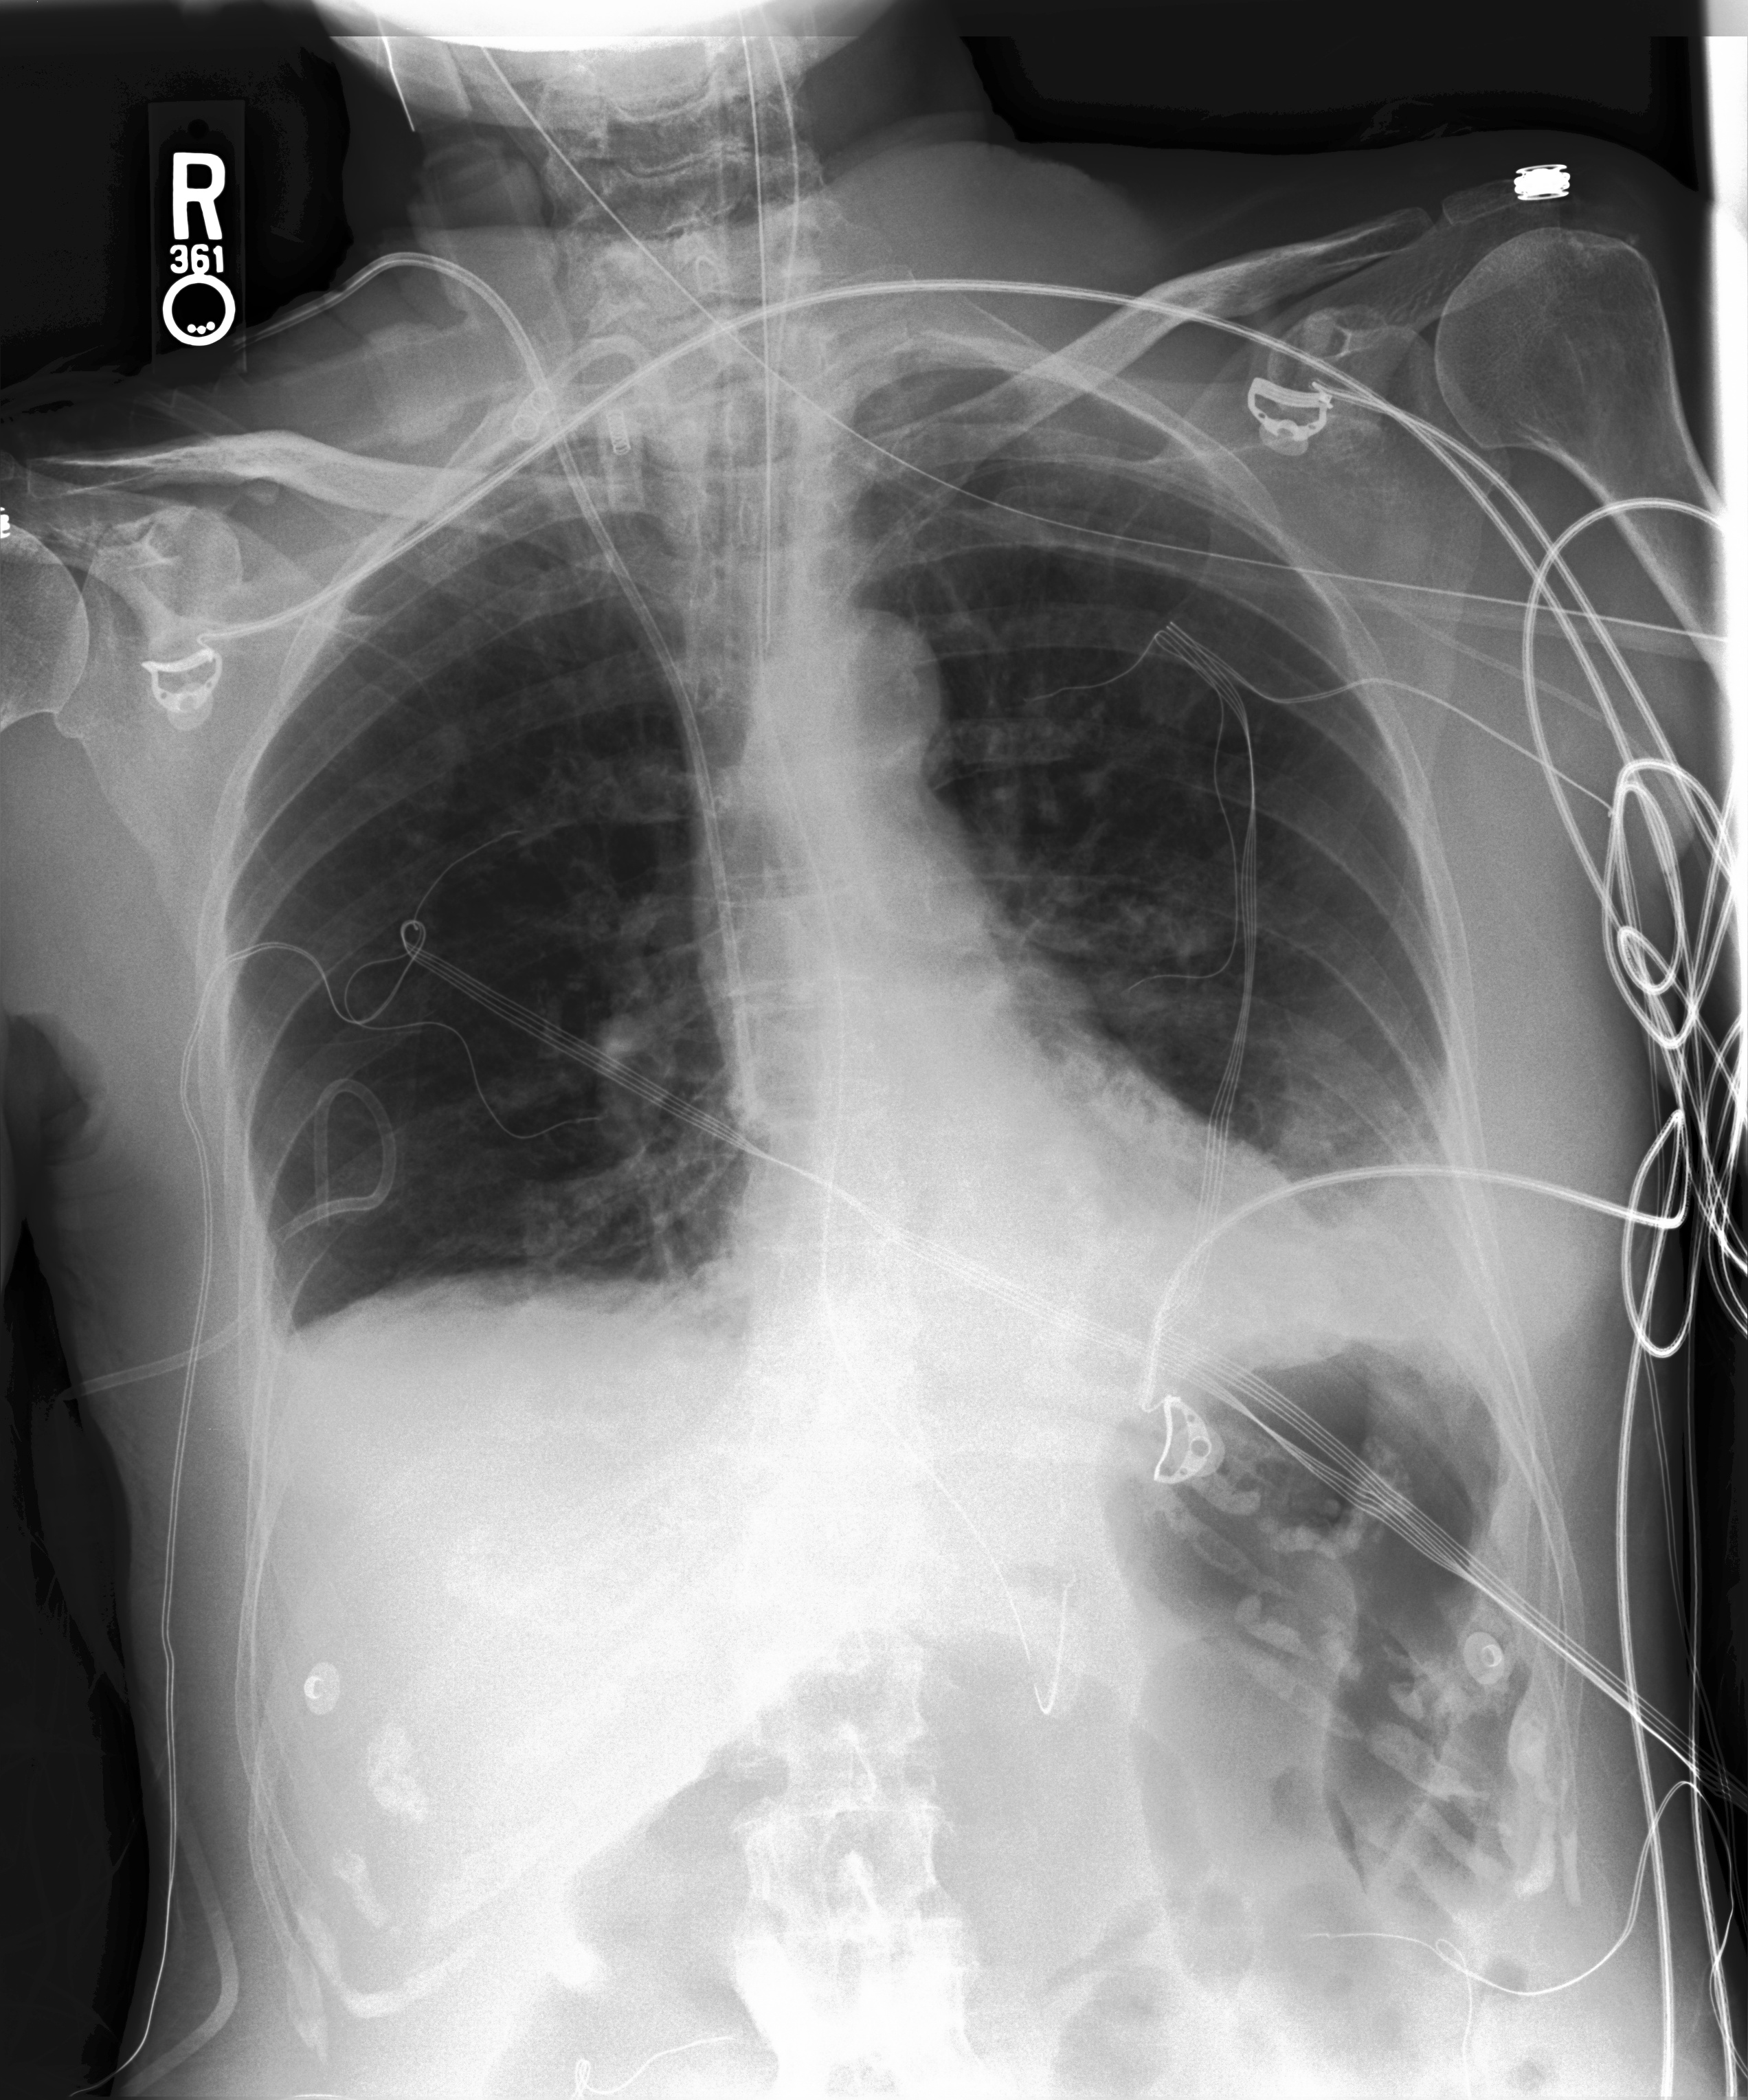

We additionally provided our model performance illustrations in Table 2 containing the original X-Ray images from the MIMIC-CXR dataset, the ground truth expert label and the model prediction (SAT + GPT-3). We manually underlined the similarities and identical diagnoses in texts to guide the eye.

Chest X-Ray Ground Truth Our predictions

[Uncaptioned image] There is decrease in now small right pleural effusion. There is no pneumothorax. There is a new right pacer pigtail catheter. Cardiomediastinal contours are unchanged. Lines and tubes are in standard position. Left lower lobe opacities, a combination of pleural effusion and atelectasis, are unchanged. uncertain pneumonia. pleural effusion present. lung opacity present. atelectasis present. bilateral pleural effusions, left greater than right. bibasilar opacities potentially atelectasis in setting of low lung volumes. infection be excluded. frontal and lateral views of chest demonstrate low lung volumes, which accentuate bronchovascular markings. there are small bilateral pleural effusions, right greater than left, with adjacent atelectasis. there is no focal consolidation pneumothorax. cardiomediastinal silhouette is within normal limits. surgical clips are seen in right upper quadrant of abdomen. aortic arch calcifications are noted.